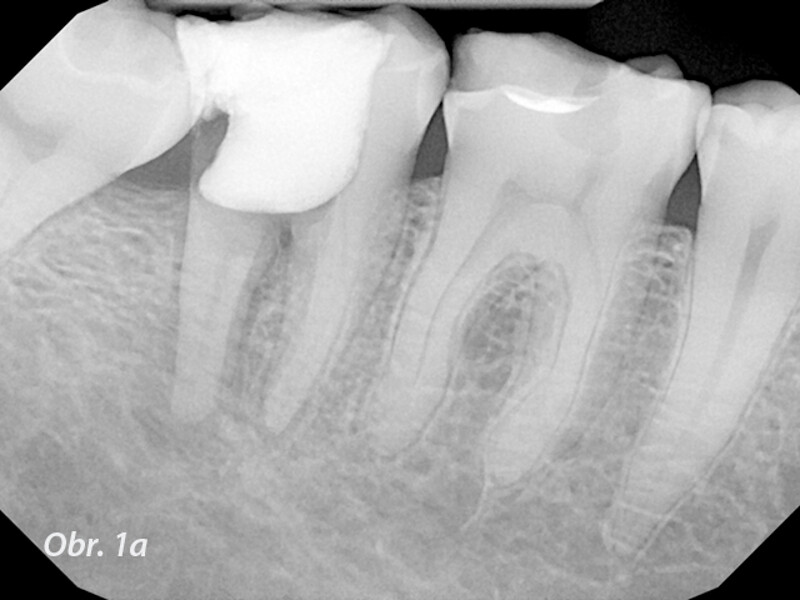

Řešení endodontických selhání